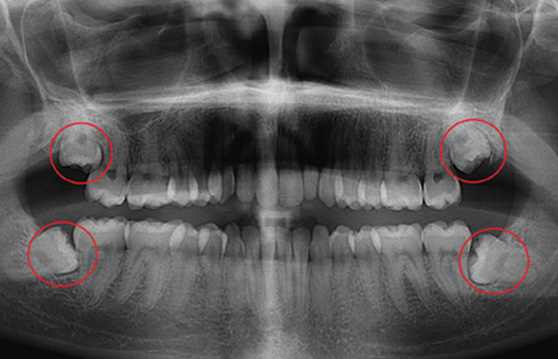

ÀÓÇöõÆ® ¼ö¼ú Àü CTÃÔ¿µÀ» ÅëÇØ ÀÕ¸ö»ÀÀÇ Á¤È®ÇÑ ¸ð¾ç°ú Å©±â µîÀ» ÀÔüÀûÀ¸·Î ÀçÇöÇÏ¿© ½Ä¸³ À§Ä¡¸¦ °áÁ¤ÇÕ´Ï´Ù.

´õÁÁÀº¼¿ïÄ¡°ú¿¡¼´Â ¿¢½º·¹ÀÌ Àåºñ, ÷´Ü CT µî »ç¶û´Ï ¹ßÄ¡ Áø´Ü¿¡ ÇÊ¿äÇÑ Ã·´Ü Àåºñ¸¦ º¸À¯Çϰí ÀÖ¾î ¾ÈÀüÇÑ »ç¶û´Ï ¹ßÄ¡°¡ °¡´ÉÇÕ´Ï´Ù.